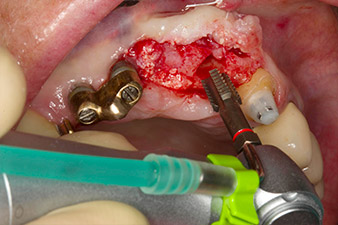

Nach primärer Abheilung werden die Weichgewebe mithilfe der basal unterfütterten Brücke ausgeformt. Zwei Monate später erfolgt die Freilegung mit einem leicht palatinal gelegten Kieferkammschnitt (Abb. 2).

Der Alveolarknochen erweist sich an Position 22 als ausreichend dimensioniert. Die Abbildungen 2 und 4 zeigen die Implantatbett-Aufbereitung, den Gewindeschnitt und die Implantation mit dem Implantmed.

Der neue Implantologiemotor wird jeweils mit den geeigneten chirurgischen Winkelstücken von W&H verwendet.

Um den parodontalen Knochenverlust auszugleichen und ein ästhetisches Ergebnis zu erreichen, wird die Implantation mit gesteuerter Knochenregeneration mit xenogenem Ersatzmaterial und einer Kollagenmembran kombiniert (Abb. 5 und 6).